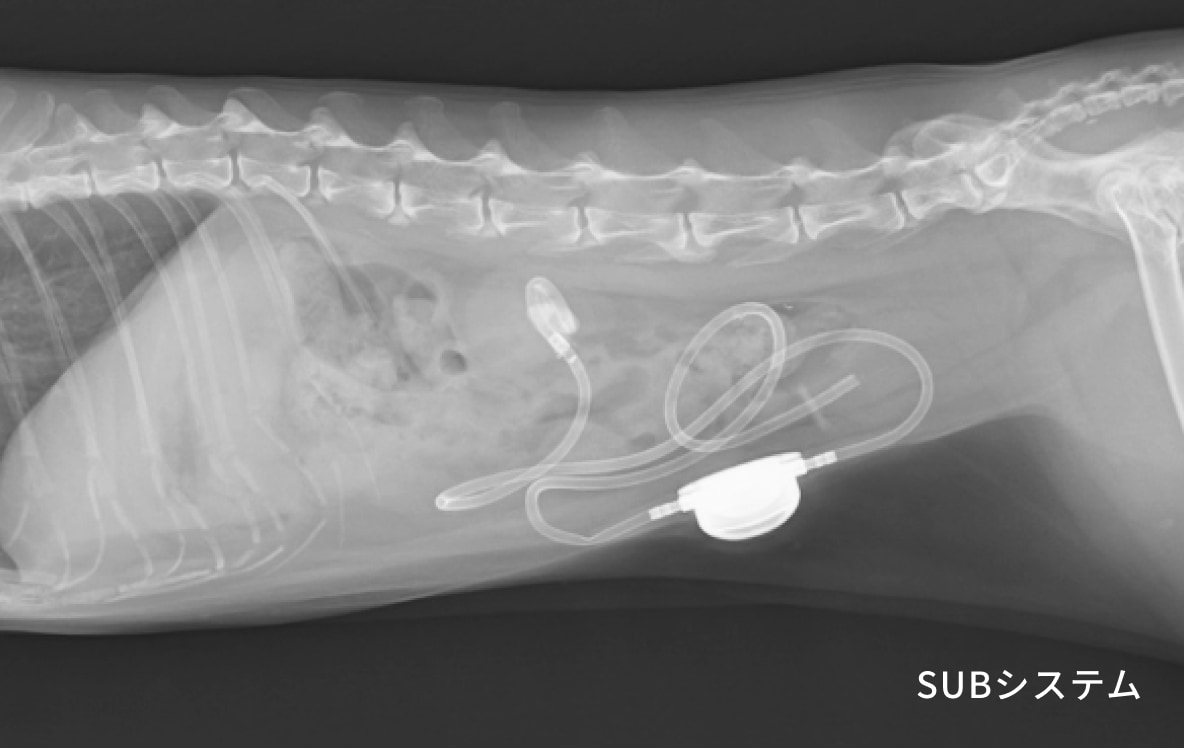

腎臓摘出、尿管吻合、SUBシステム(尿管結石治療に使用する特殊ステント)など多岐にわたる外科手術も実施しています。